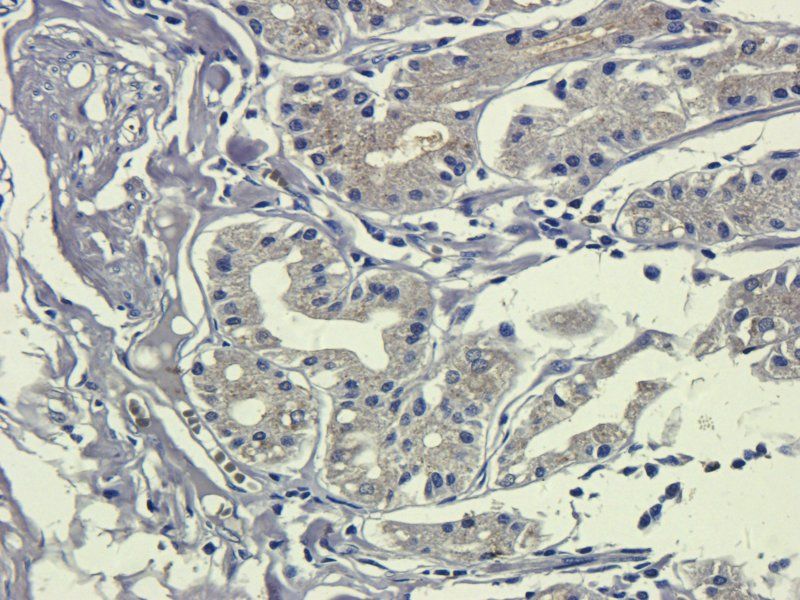

100 μg - FOXP3 antibody [orb34127]Featured

ELISA, ICC, IF, IHC-P, WB

Human, Mouse, Rat

Rabbit

Polyclonal

Unconjugated

100 μg - OPG antibody [orb247239]Featured